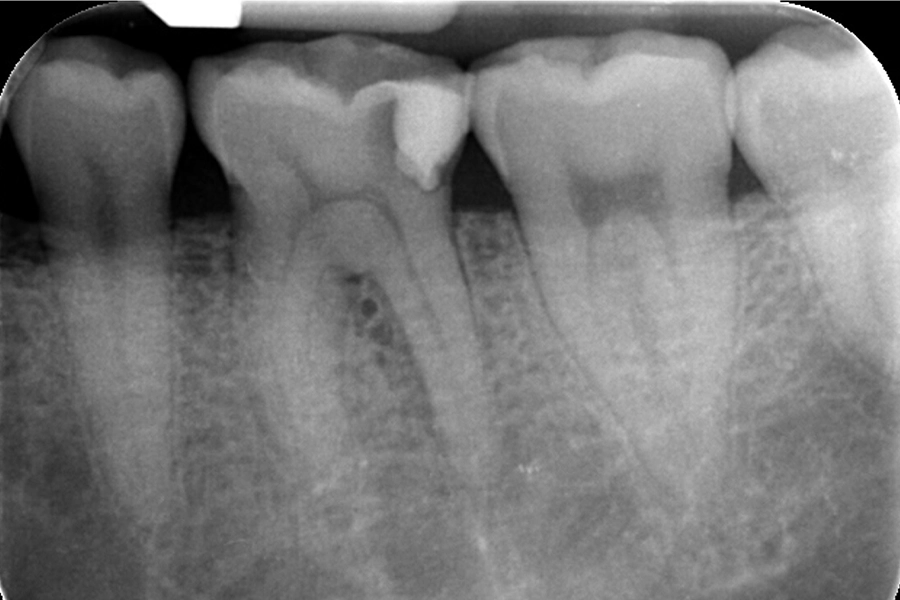

治療前